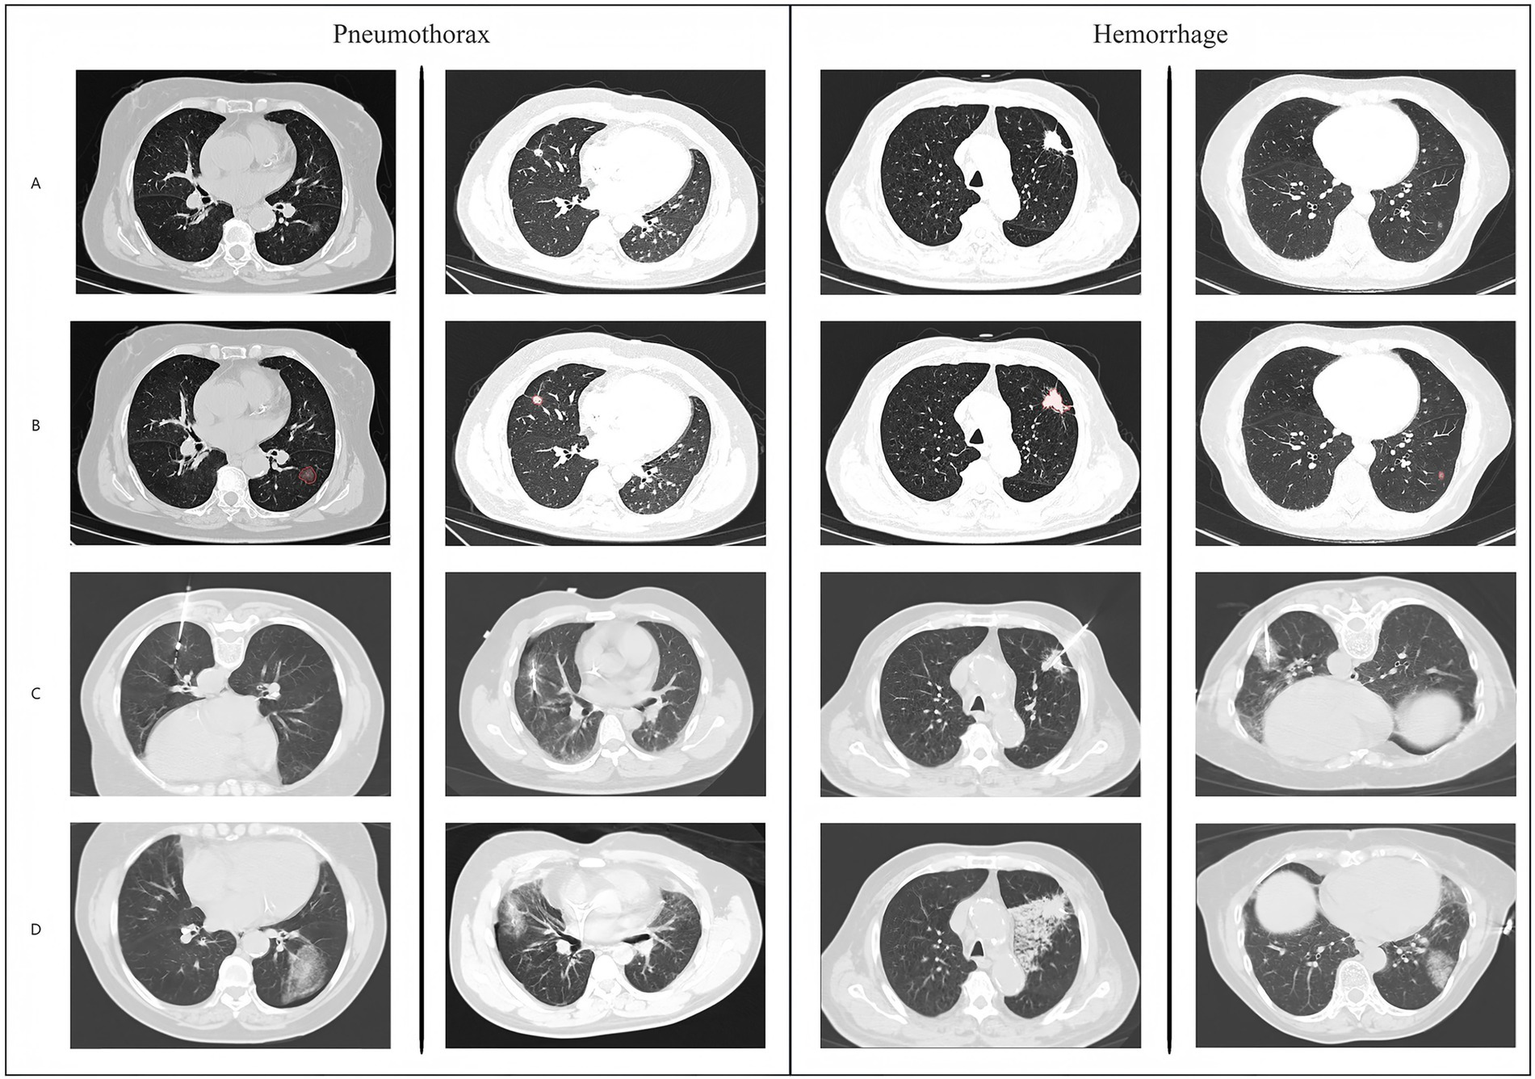

Figure 4

Overall network model architecture diagram.

Figure 5

Schematic diagram and example data of model operation results.